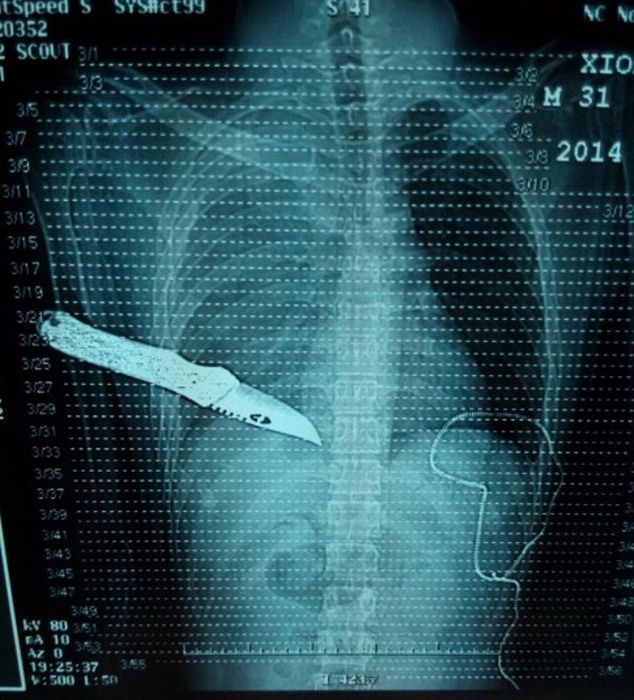

Рентгеновские снимки людей, которые умудрились сами или с чужой помощью разместить внутри своего организма разные посторонние предметы. От вилок и ножей до пуль и бензопилы (!!!). По этическим соображениям обычные снимки таких травм и повреждений выкладывать нельзя, зато рентгеновские можно – на них травмы видны достаточно условно, хоть и очень понятно.